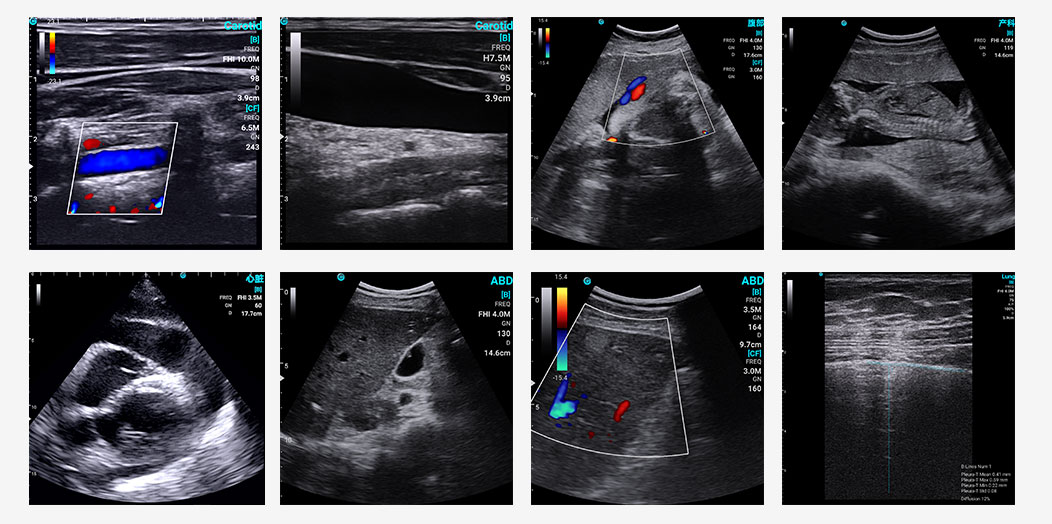

SonoEye stood out in B-mode image quality, ranking among the top performers. This is a key factor in its success in clinical applications, as?high resolution and?optimal contrast?are vital for accurate diagnoses.?As the study mentioned, a convex transducer delivers superior B-mode images for abdominal ultrasound compared to “all-in-one” transducers designed for multiple clinical applications. SonoEye also boasts competitive image quality in Color Doppler Mode, PW Mode and CPA/DPD Mode, ensuring physicians get precise and clear visuals every time.

Exemplary sonographic images of SonoEye in B mode, C mode